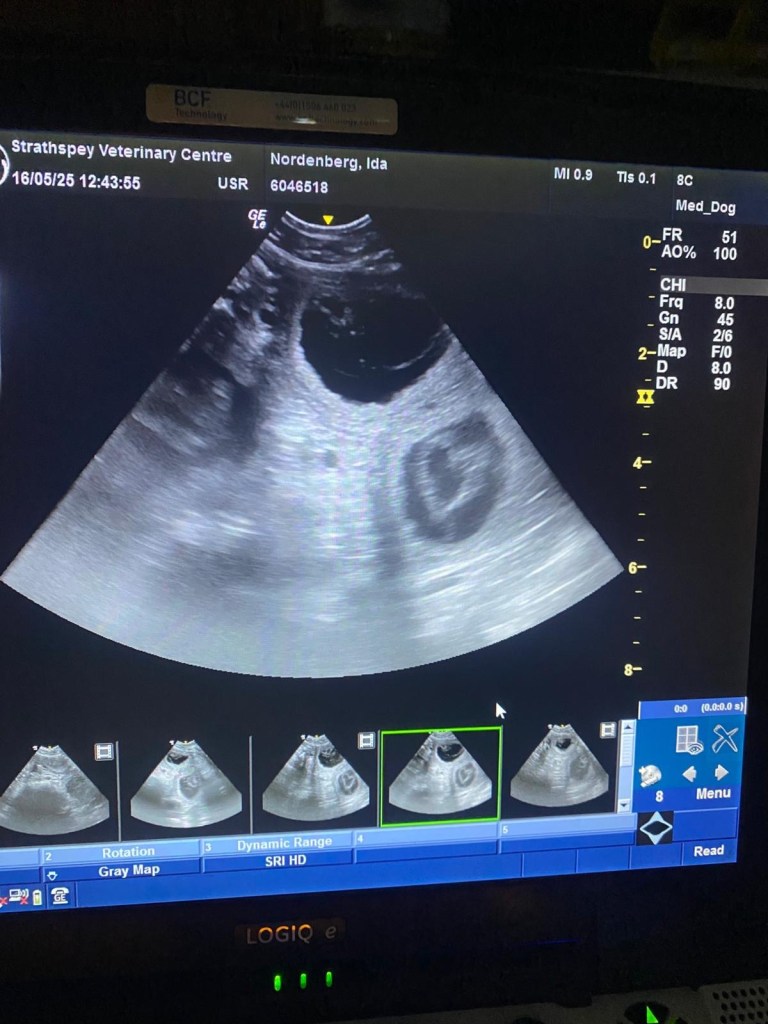

Pregnancy confirmed! May 16, 2025May 16, 2025avonwolf Leave a comment The P-litter is on route🤩 Share this: Share on X (Opens in new window) X Share on Facebook (Opens in new window) Facebook Like Loading... Related